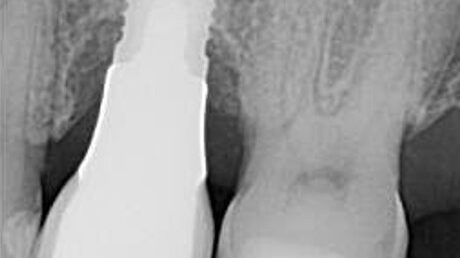

Iatrogenic Screw Retrieval of a Poorly Placed TSV Implant, Creating a Type VI Screw Recovery Case – 0040

This implant case showcases an example of an Iatrogenic screw retrieval of a poorly placed TSV implant, Creating a Type VI Screw Recovery Case.